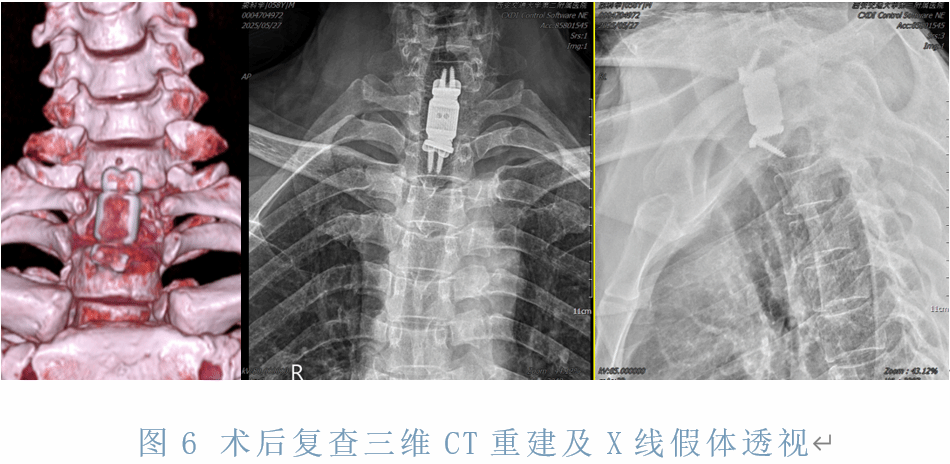

手术在“C”臂X线透视引导下,精确定位。王栋主任主刀、赵波副教授、李宇欢、赵敏超等医生紧密合作,在麻醉医师袁浩峥,手术室护士董春力、祁海浪熟练的配合下,将突向椎管、压迫脊髓的椎体细致切除,将可动人工椎体精准植入进行胸1重建,密切有序的手术处理,历时2个小时。顺利完成了颈胸交界处脊髓、神经根的减压和胸1的仿生重建。

术后患者各项监测指标正常,麻醉清醒后患者胸背部疼痛及双上肢麻木症状完全缓解,病情平稳。术后3天佩戴支具可下地行走。